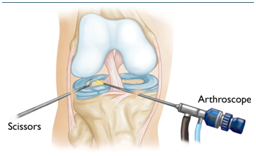

半月板损伤怎么样来修复呢,手术怎么做呢?

手术是通过关节镜来进行的,是非常微创的手术。一般两个小于1cm的切口就可以解决了。大部分患者仅适用两个小于1cm的切口,而且位于膝眼位置,

不仔细看看不出来。利用关节镜技术把损伤的半月板修整缝合加固。